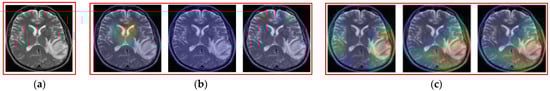

As shown in Section 4, our proposed method outperformed previous methods for brain tumor image classification using a small training dataset. For demonstration purposes, we show some examples in which our proposed method (based on the weighted-SUM rule) helps to enhance the classification performance of individual classifiers in Figure 12. We can observe from this figure that, although an individual method (among three methods) can falsely classify an image, the fusion with the result of other classifiers helps to correct that error and consequently enhances the classification performance of the overall system.

To investigate the internal functioning of the MLP-based method for the classification problem, we extracted the class activation map (CAM) image [51] of example input images using a CNN-based network (feature extracted by CNN and followed by classification by MLP) presented in Figure 4, as shown in Figure 13 and Figure 14, for the case where the input image is a tumor image (Figure 13) and for the case where the input image is a non-tumor image (Figure 14). As shown in Figure 13, the MLP network pays more attention to the tumor region (higher weight) than the other regions for making a decision on the input image belonging to the tumor class (Figure 13c), whereas it uniformly analyzes the overall input image for making a decision on the input image belonging to the non-tumor class (Figure 13b). When the input image is a non-tumor image, as shown in Figure 14, the networks pay attention to the entire brain region for making decisions on the input image belonging to the non-tumor class, whereas they pay attention to some high-frequency regions such as the skull or brain boundary region to make decisions on the input image belonging to a tumor class. From these figures, we see that the MLP network pays attention to tumor regions or high-frequency regions for making decisions on input images belonging to the tumor region and pays uniform attention to the entire brain region to make decisions on input images belonging to the non-tumor class.